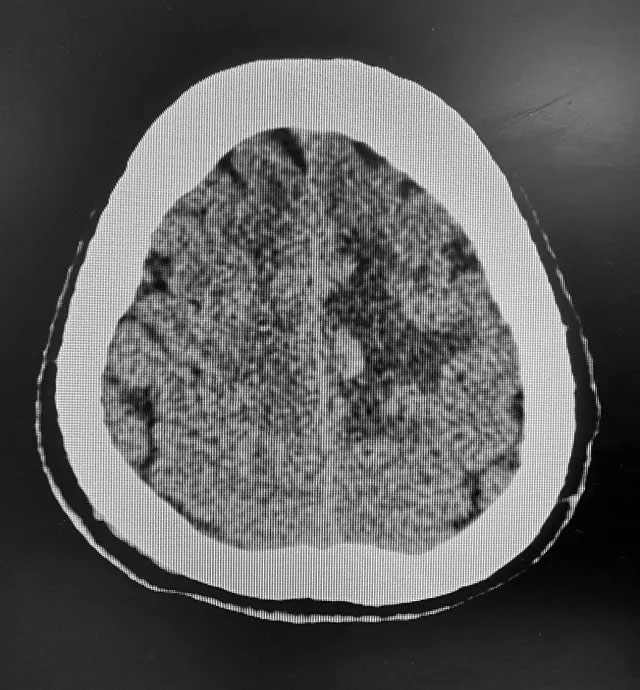

▲患者CT檢查影像

64歲患者蘇大爺(化名)今年三月份突然無明顯誘因出現(xiàn)四肢乏力,不能活動,送當?shù)蒯t(yī)院經(jīng)頭顱CT檢查診斷為“出血性腦梗死”。經(jīng)治療,患者雙上肢活動改善,雙下肢仍不能活動。家屬為求進一步治療轉入上海藍十字腦科醫(yī)院。

患者三年前曾患腦溢血,既往高血壓病史五年,未長期有效控制,高血壓3級,最高血壓收縮壓224毫米汞柱,舒張壓118毫米汞柱。雙下肢肌力0級,肌張力高。頭顱磁共振顯示:左側額頂葉鐮旁亞急性腦梗死伴出血。